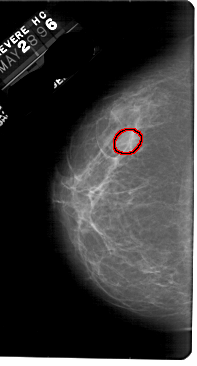

FILE: A_1833_1.LEFT_CC.OVERLAY

TOTAL_ABNORMALITIES 1

ABNORMALITY 1

LESION_TYPE MASS SHAPE LOBULATED MARGINS OBSCURED

ASSESSMENT 3

SUBTLETY 3

PATHOLOGY BENIGN

TOTAL_OUTLINES 1

BOUNDARY